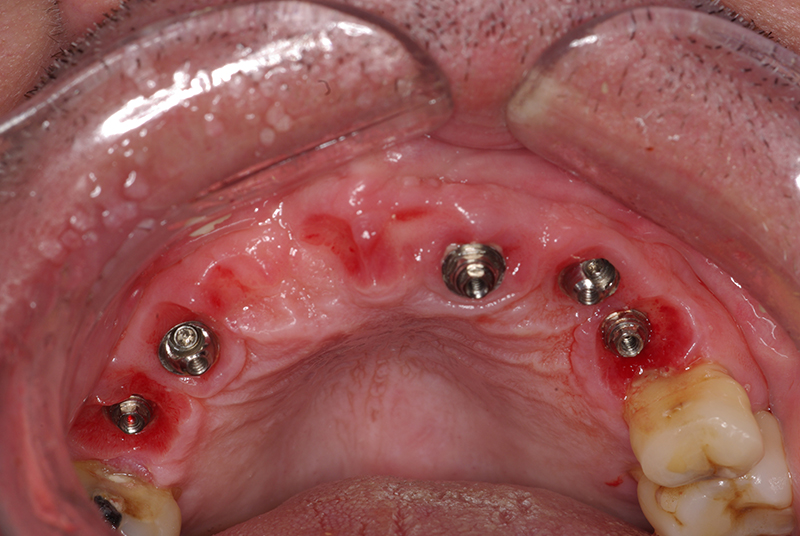

Na Clínica Pontes Odontologia, somos referência em implantes dentários em Fortaleza, oferecendo tratamentos de alta qualidade e tecnologia de ponta. Os implantes dentários são estruturas de titânio posicionadas cirurgicamente no osso maxilar ou mandibular para substituir as raízes dos dentes ausentes. Essa técnica permite a fixação de próteses personalizadas, restaurando a função mastigatória, a estética e a autoestima dos nossos pacientes.

Utilizamos a tecnologia CAD CAM, um sistema avançado que possibilita a confecção precisa das próteses dentárias diretamente sobre os implantes. Esse método inovador garante um ajuste perfeito, um resultado estético superior e proporciona muito mais conforto e durabilidade. Com o CAD CAM, nossos pacientes contam com um processo mais rápido e previsível para alcançar o sorriso desejado.